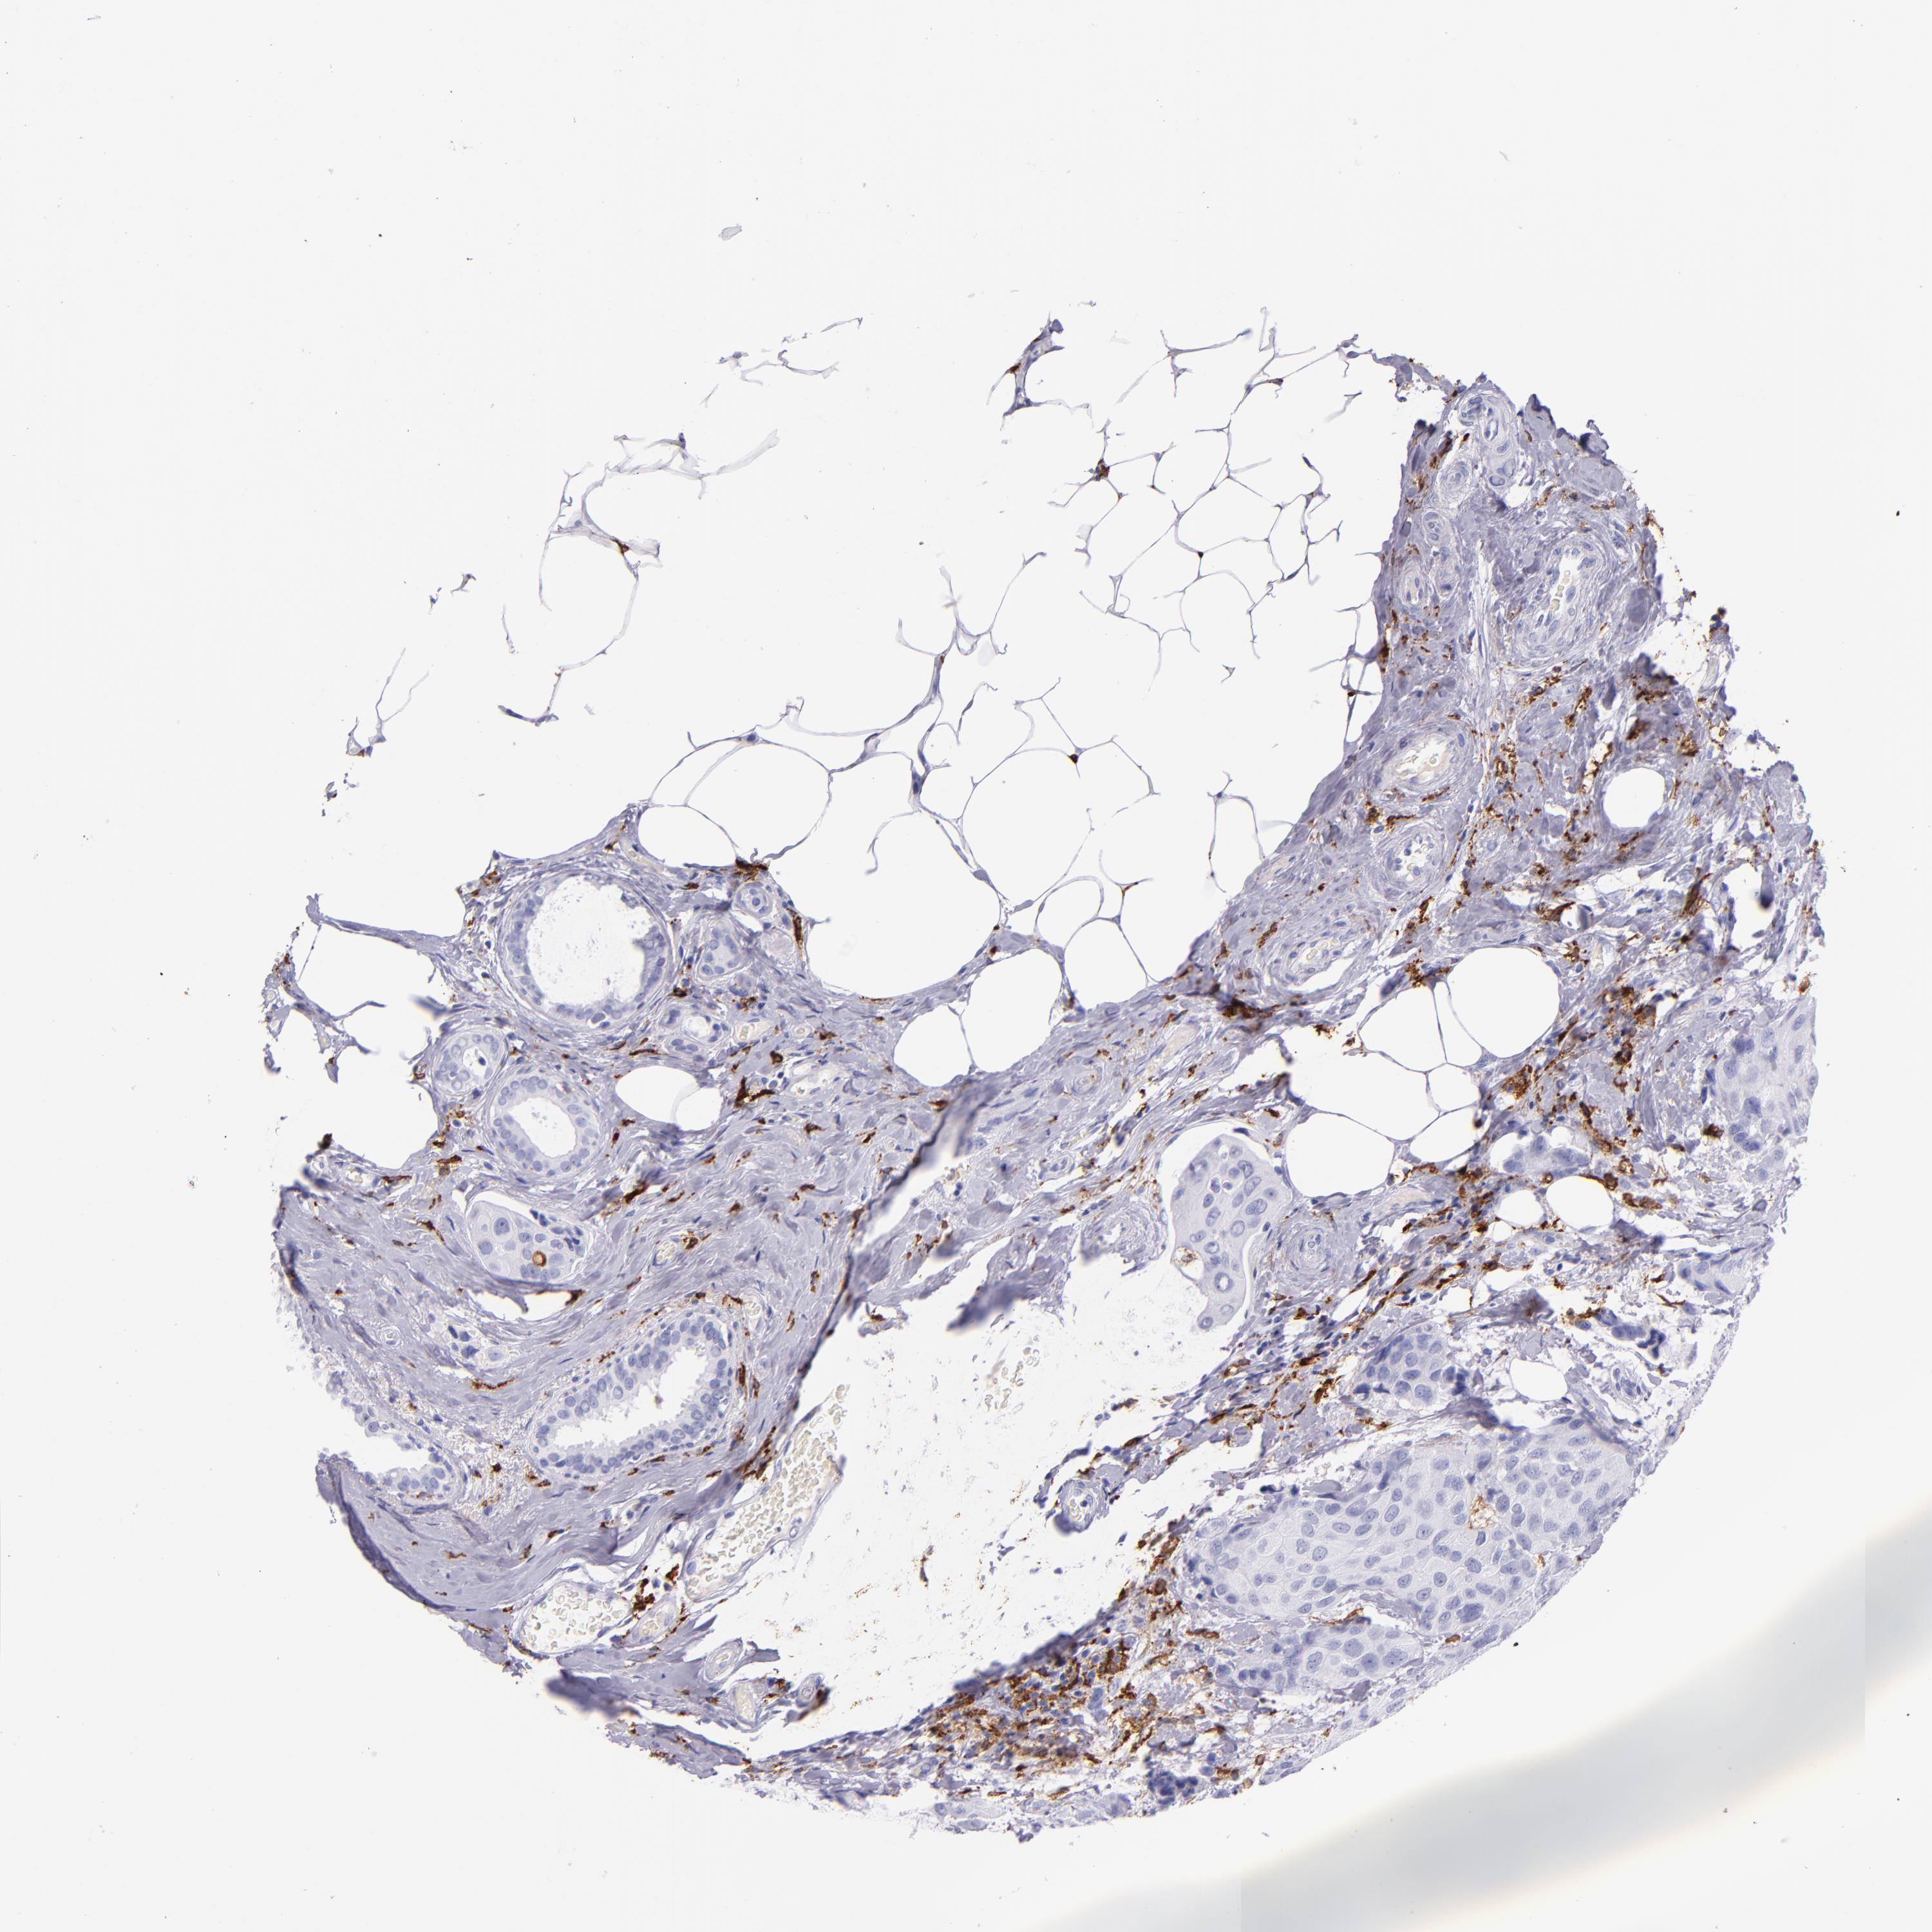

CD163